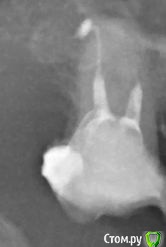

ЛюдаБС Опубликовано 21 февраля, 2019 Поделиться Опубликовано 21 февраля, 2019 Здравствуйте! Вот такой зуб,Долго стоял по старой пломбой, было многомесячное повреждение десны с кровоточивостью. Запломбировали каналы, хожу, жду реакции зуба. Если оставим (доктор склоняется к этому), будем под коронку ставить. Объективно мне намного лучше, после временной пломбировки каналов поднималась температура 37,9, пришлось антибиотики пить, очень болела десна. Сейчас отека нет (был дня 4), боли нет, десна практически нормальная, динамика по ощущениям положительная. Но! Под этим зубом нет зуба-оппонента. Т.е. я не могу оценить реакцию на накусывание. Надавливаю - вроде что-то чувствую, не боль в явной форме, а давление какое-то. На постукивание реакции нет. Вопрос - зуб он вообще жилец?P.S. Я пациент-паникер, ну так получилось. Уже сто раз подумала, что если бы удалила, уже бы все зажило и вообще хорошо было, а уж дешевле насколько. Ссориться с доктором и хамить ему сомнениями не хочу, да и жаловаться вроде не на что. Но и невозможность оценить состояние зуба доступными мне способами пугает. Буду признательна за комментарии. Ссылка на комментарий

suballex Опубликовано 22 февраля, 2019 Поделиться Опубликовано 22 февраля, 2019 . Уже сто раз подумала, что если бы удалила, уже бы все зажило и вообще хорошо было, а уж дешевле насколько. Буду признательна за комментарии.Если бы вы удалили - поставили бы потом имплант, с ценником от 40 к, в регионах. И еще синуслифтинг бы понадобился с высокой вероятностью. Это еще от 15. Причем, в очень средней клинике. Так что, не нужно горячиться.По вашему снимку, можно сказать с уверенностью, что зуб у вас есть. Больше ничего определенного, к сожалению. Ссылка на комментарий